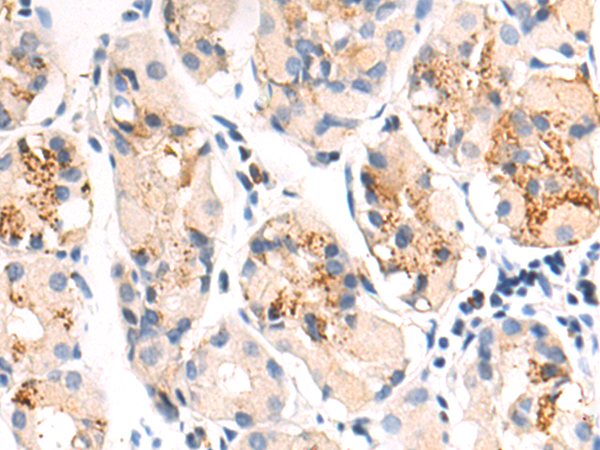

分类: 科研抗体货号: P00547别名: MUC-20应用: IHC反应种属: Human